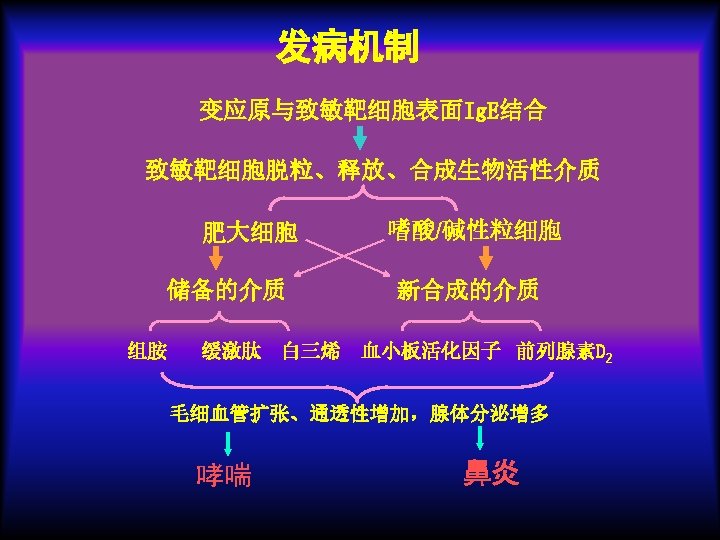

Pathology: Type allergy Allergic inflammation: Predominant T cells & eosinophilic cells infiltrate.